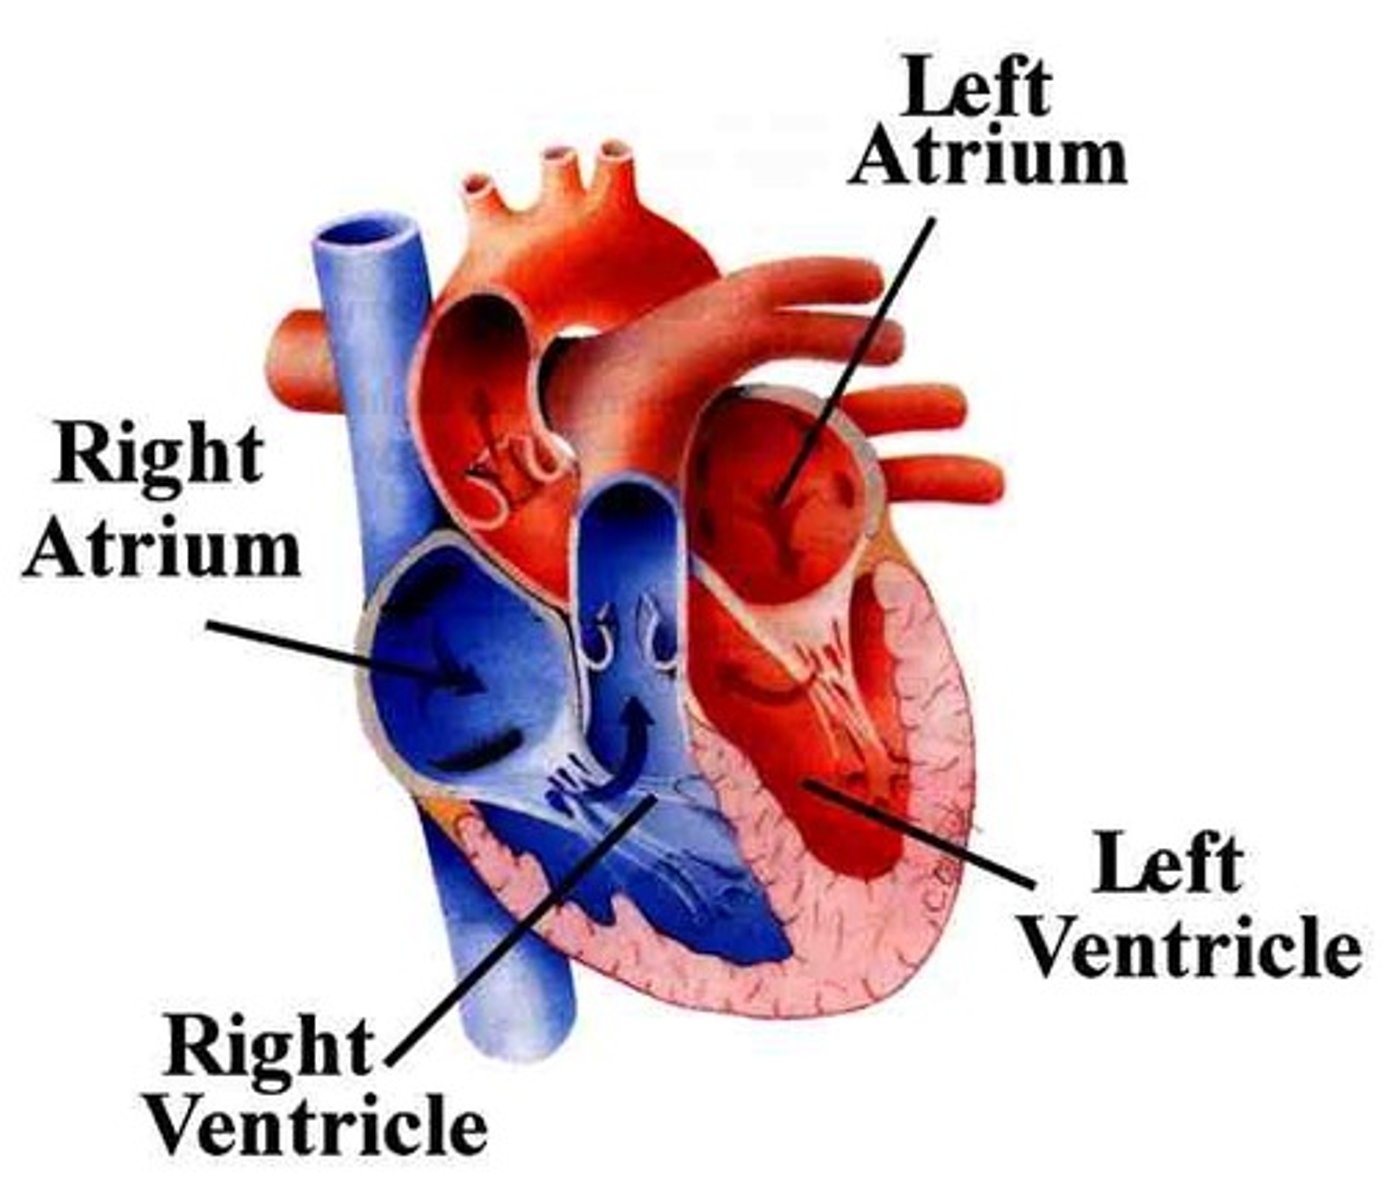

Two atria; right and left (receiving chambers)

Two ventricles; right and left (discharging chambers)

Name the four chambers

The right atrium receives deoxygenated blood from:

The four pulmonary veins (right superior, right inferior, left superior, left inferior)

The left atrium receives oxygenated blood from:

From: Left atrium through the bicuspid valve

To: Aorta through semilunar valve to systemic system

The left ventricle receives blood from:

and sends it:

From: Right atrium through tricuspid valve

To: Pulmonary trunk (artery) through semilunar valve to lungs then pulmonary veins

The right ventricle receives blood from:

and sends it: